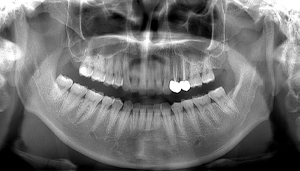

右下の親知らず抜歯症例

- 抜歯前写真(レントゲン)

- 抜去歯の写真

| 年齢 | 20代・男性 |

|---|---|

| 主訴 | 右下に痛みがある 右下8抜歯 |

| 治療期間 | 1日 |

| 費用 | 約6,500円(2022年6月現在) |

| 治療内容 | 右下8番が真横に生えているのと右上8番が下の歯茎に噛んできていて痛みがある状態でした。 両方抜かないと改善されないため同日に上下2本の抜歯を行いました。 |

| リスク・副作用 | 顎の神経が近いため、 抜歯後に麻痺や知覚異常をおこす場合があります。 抜歯後2,3日が腫れのピークになり発熱、内出血が出ることがありますが、痛み止めを飲んでしのげる場合がほとんどです。 抜歯後は細菌感染のリスクがあるため抜いたところを舌や指で刺激しないように注意してもらいます。 激しくゆすぎすぎるとドライソケットになるためうがいは優しくするようにしてもらいます。 |